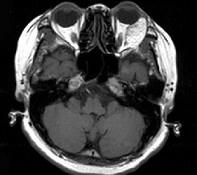

问题 女,52岁,左眼球突出二十余年, T3、T4均正常,影像检查如图所示,应诊断为 ( )

选项 A、血管瘤 B、炎性假瘤 C、脂肪瘤 D、畸胎瘤 E、错构瘤

答案 E